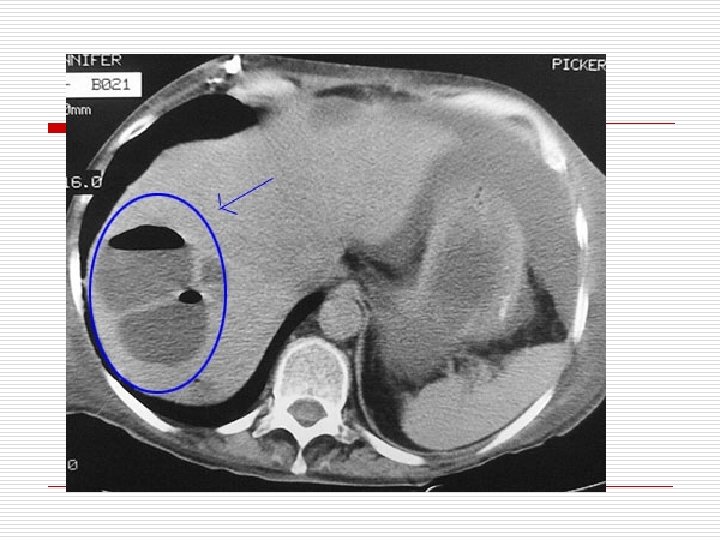

Абсцесс печени кт

Абсцесс печени кт 109 фото